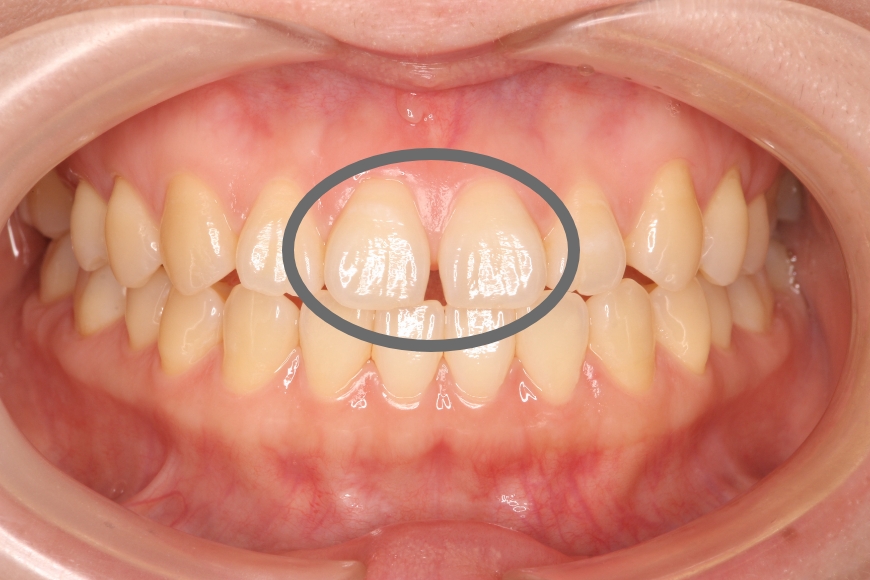

38歳女性 前歯正中離開に対するダイレクトボンディング

治療前

治療内容 前歯の「すきっ歯」が気になるとのことで来院されました。

矯正治療、セラミック治療、ダイレクトボンディング治療を提案しました。治療期間の短縮と歯質の保存を優先し、ダイレクトボンディングによる治療を選択されました。

ラバーダム防湿下で専用のコンポジットレジンを段階的に充填し形態・色調を再現しました。(歯を削っていません)

治療回数 通院回数:1回

治療費用(総額)

88,000

(1本44,000円×2本分。治療時の金額であり、時期や手法により異なる場合があります。)